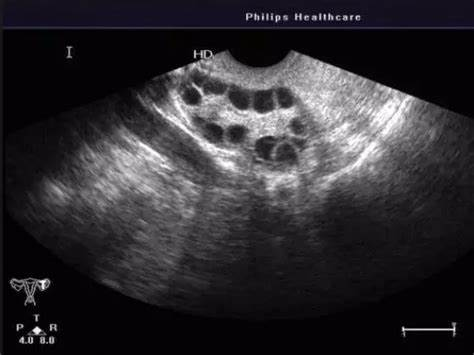

3. B超监测卵泡发育

通过阴道超声(B超),可以直接观察卵泡的大小、形状和生长趋势。

优质卵泡通常大小均匀、形状饱满,直径在18~25mm之间。如果卵泡小于18mm,可能发育不成熟;大于25mm,则可能黄素化而无法正常排卵。

需要注意的是,B超只能观察卵泡而非卵子本身。卵泡形状与大小仅能间接反映卵子的质量。因此,建议选择固定的医生进行多次监测,以获得更精准的评估结果。